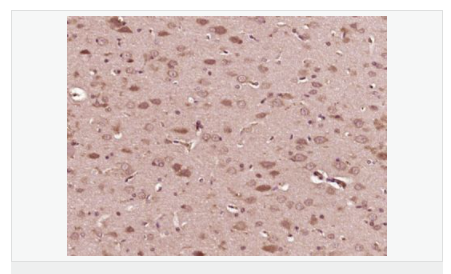

| 產(chǎn)品應用 | WB=1:500-2000 ELISA=1:5000-10000 IHC-P=1:100-500 IHC-F=1:100-500 Flow-Cyt=2ug/Test ICC=1:100-500 IF=1:100-500 (石蠟切片需做抗原修復) not yet tested in other applications. optimal dilutions/concentrations should be determined by the end user. |

| 產(chǎn)品介紹 | Converts sphingomyelin to ceramide. Also has phospholipase C activities toward 1,2-diacylglycerolphosphocholine and 1,2-diacylglycerolphosphoglycerol. Isoform 2 and isoform 3 have lost catalytic activity. Involvement in disease: Defects in SMPD1 are the cause of Niemann-Pick disease type A (NPDA) ; also known as Niemann-Pick disease classical infantile form. It is an early-onset lysosomal storage disorder caused by failure to hydrolyze sphingomyelin to ceramide. It results in the accumulation of sphingomyelin and other metabolically related lipids in reticuloendothelial and other cell types throughout the body, leading to cell death. Niemann-Pick disease type A is a primarily neurodegenerative disorder characterized by onset within the first year of life, mental retardation, digestive disorders, failure to thrive, major hepatosplenomegaly, and severe neurologic symptoms. The severe neurological disorders and pulmonary infections lead to an early death, often around the age of four. Clinical features are variable. A phenotypic continuum exists between type A (basic neurovisceral) and type B (purely visceral) forms of Niemann-Pick disease, and the intermediate types encompass a cluster of variants combining clinical features of both types A and B. Function: Converts sphingomyelin to ceramide. Also has phospholipase C activities toward 1,2-diacylglycerolphosphocholine and 1,2-diacylglycerolphosphoglycerol. Isoform 2 and isoform 3 have lost catalytic activity. Subunit: Monomer. Subcellular Location: Lysosome. DISEASE: Defects in SMPD1 are the cause of Niemann-Pick disease type A (NPDA) [MIM:257200]; also known as Niemann-Pick disease classical infantile form. It is an early-onset lysosomal storage disorder caused by failure to hydrolyze sphingomyelin to ceramide. It results in the accumulation of sphingomyelin and other metabolically related lipids in reticuloendothelial and other cell types throughout the body, leading to cell death. Niemann-Pick disease type A is a primarily neurodegenerative disorder characterized by onset within the first year of life, mental retardation, digestive disorders, failure to thrive, major hepatosplenomegaly, and severe neurologic symptoms. The severe neurological disorders and pulmonary infections lead to an early death, often around the age of four. Clinical features are variable. A phenotypic continuum exists between type A (basic neurovisceral) and type B (purely visceral) forms of Niemann-Pick disease, and the intermediate types encompass a cluster of variants combining clinical features of both types A and B. Defects in SMPD1 are the cause of Niemann-Pick disease type B (NPDB) [MIM:607616]; also known as Niemann-Pick disease visceral form. It is a late-onset lysosomal storage disorder caused by failure to hydrolyze sphingomyelin to ceramide. It results in the accumulation of sphingomyelin and other metabolically related lipids in reticuloendothelial and other cell types throughout the body, leading to cell death. Clinical signs involve only visceral organs. The most constant sign is hepatosplenomegaly which can be associated with pulmonary symptoms. Patients remain free of neurologic manifestations. However, a phenotypic continuum exists between type A (basic neurovisceral) and type B (purely visceral) forms of Niemann-Pick disease, and the intermediate types encompass a cluster of variants combining clinical features of both types A and B. In Niemann-Pick disease type B, onset of the first symptoms occurs in early childhood and patients can survive into adulthood. Similarity: Belongs to the acid sphingomyelinase family. Contains 1 saposin B-type domain. SWISS: P17405 Gene ID: 6609 Database links: Entrez Gene: 100720041 Guinea pig Entrez Gene: 6609 Human Entrez Gene: 20597 Mouse Entrez Gene: 100353898 Rabbit Omim: 607608 Human SwissProt: P17405 Human SwissProt: Q04519 Mouse Unigene: 498173 Human Unigene: 4628 Mouse Unigene: 485064 Mouse Unigene: 18277 Rat Important Note: This product as supplied is intended for research use only, not for use in human, therapeutic or diagnostic applications. ASM酸性神經(jīng)鞘磷脂酶是ASMase神經(jīng)鞘磷脂酶最重要的一個(gè)亞型,是細胞膜的重要組成成分。ASM在細胞凋亡、調節腫瘤細胞生長(cháng)、參與Fas信號系統傳遞等方面均可發(fā)揮重要作用。 |